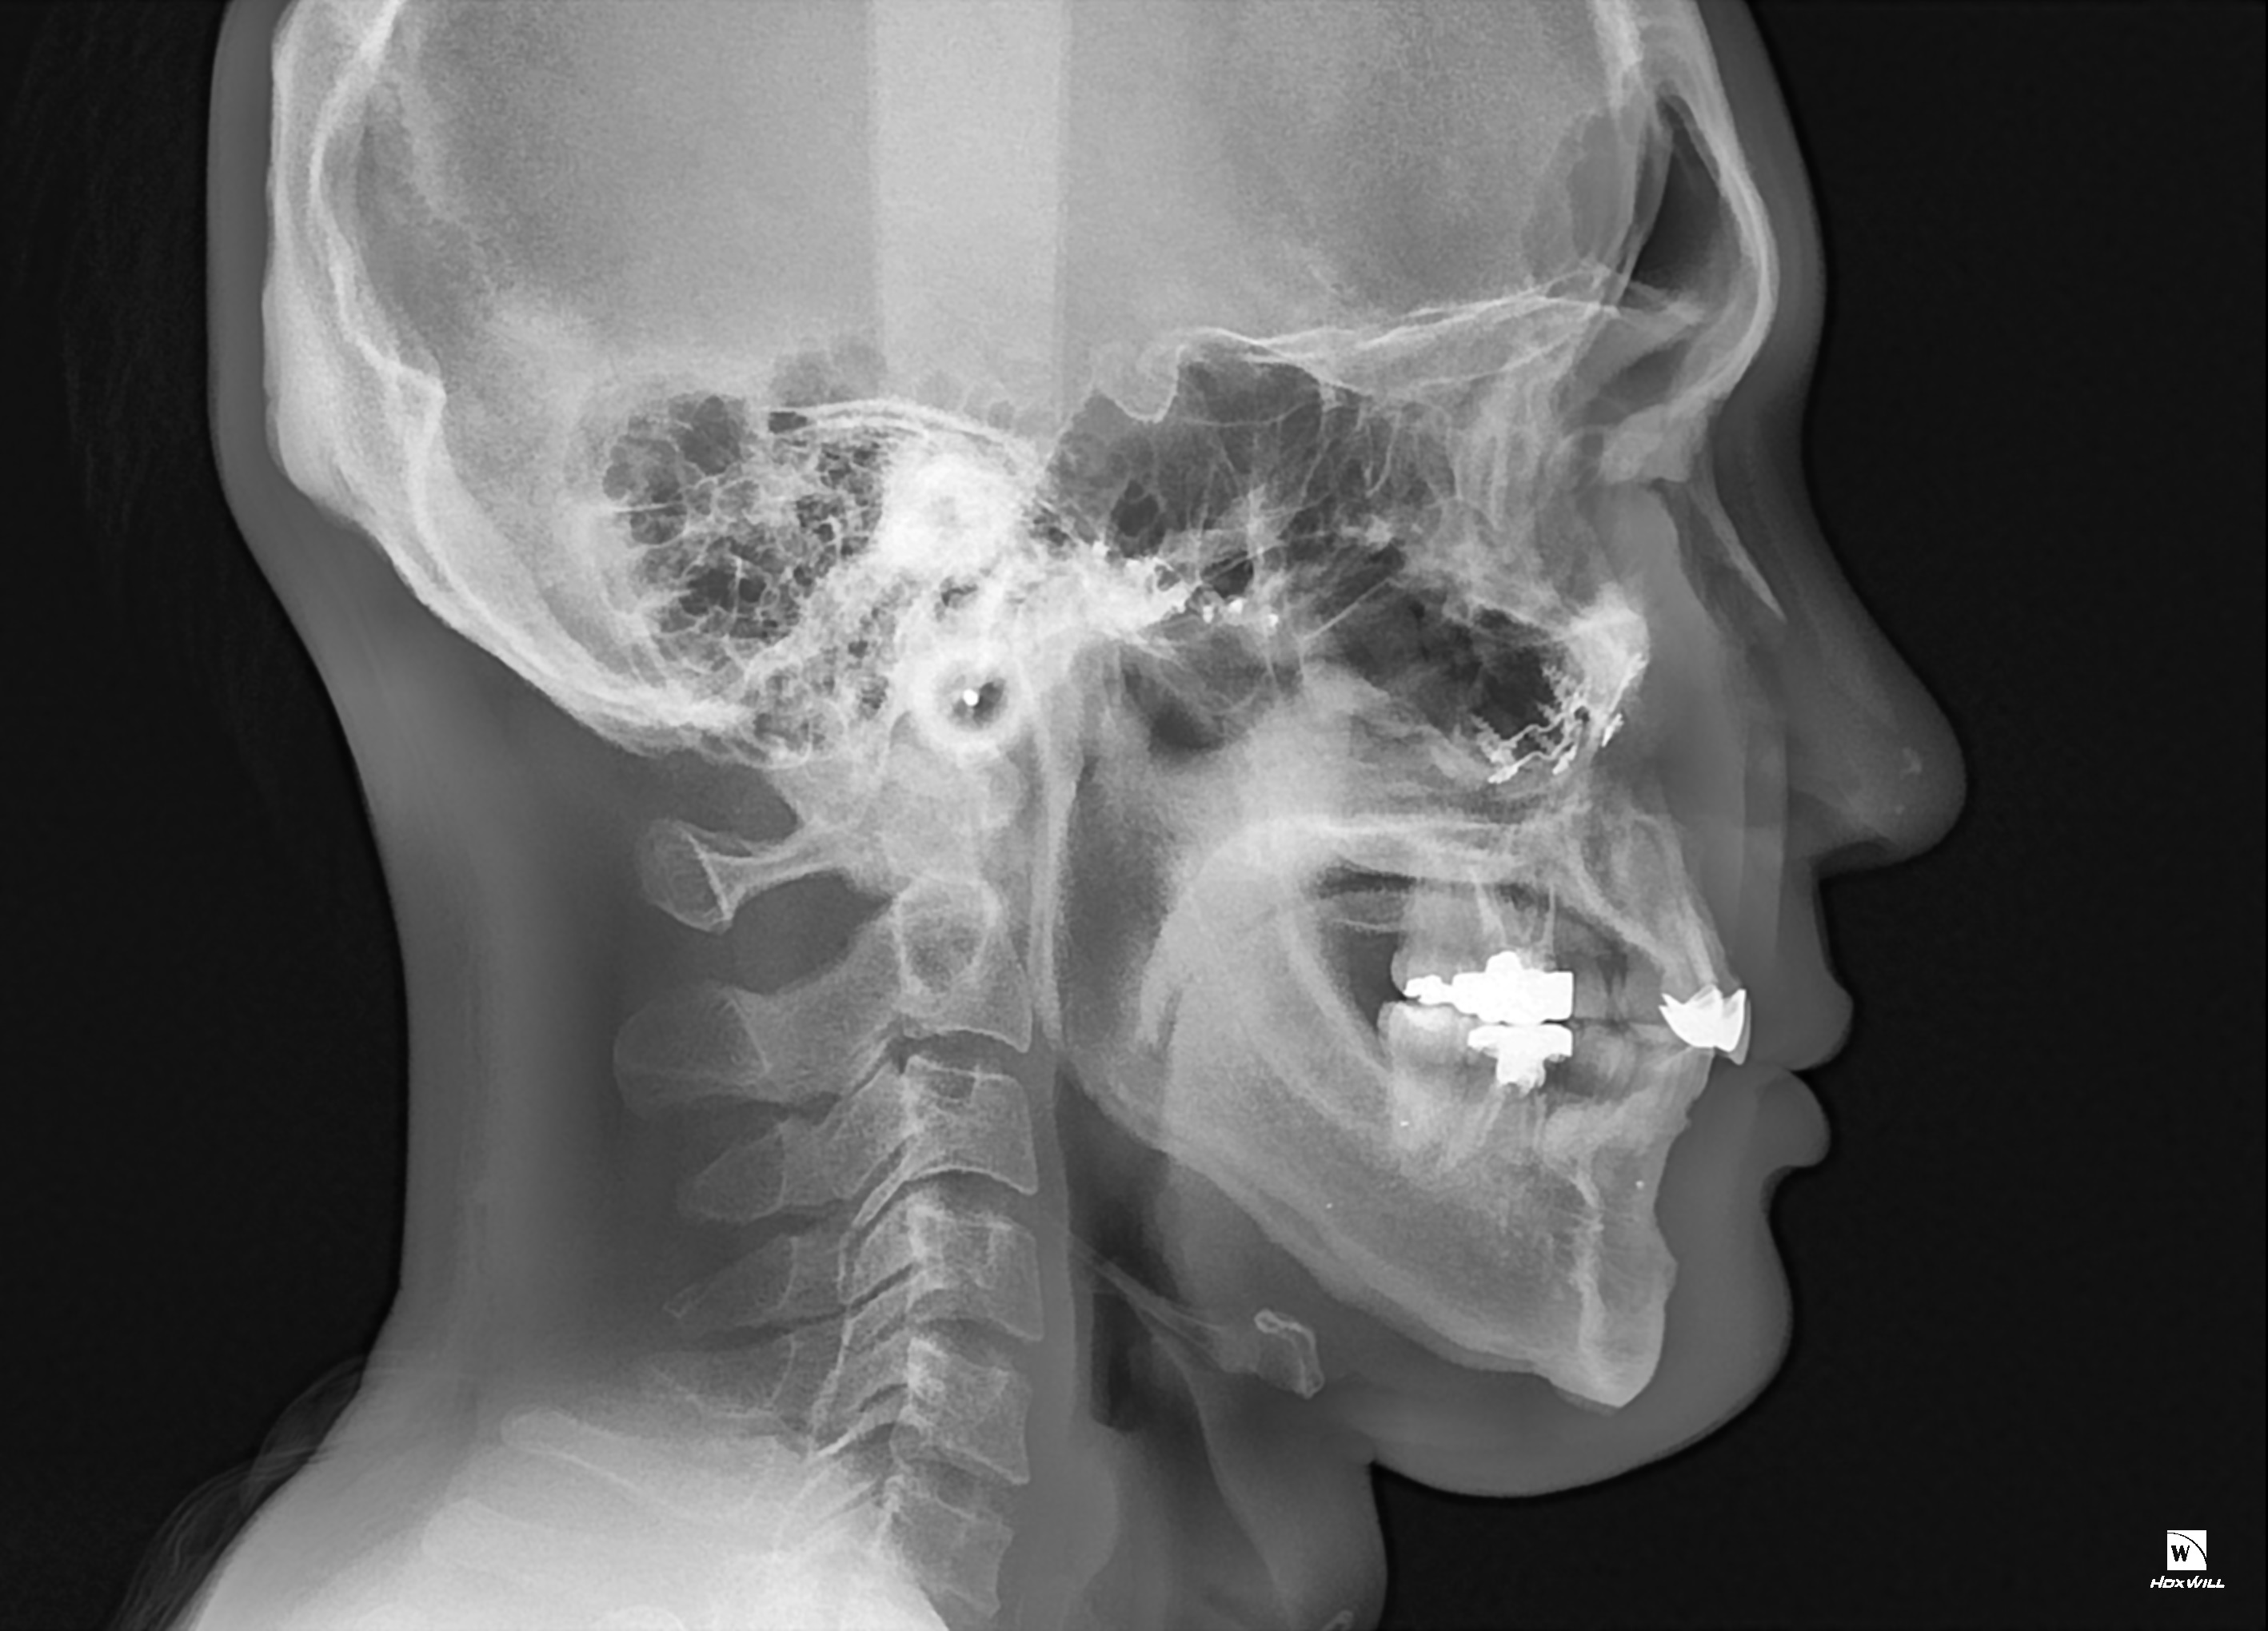

1. 현재 제가 수술 전후 ct를 올리겠습니다

2. 일차 양악 수술후 경미한 주걱턱 때문에 쉐이빙을 했는데 효과는 미미했습니다 진짜 쉐이빙은 효과가 미흡

3. 그 후 어드벤스를 3mm정도 했습니다

4. 현재 주걱턱 처럼 보여서 돌아버리겠습니다..

5. 음 어느 선생님 말을 빌리면 턱끝 절골라인이 너무 아래서 절골되어서 그런거다 신경선으로 부터 5~10mm정도 아래서 절골후 약간 사선으로 2mm 정도만 전진시키면 두꺼운 근육이 얇아지면서 좀 편해진다 이게 맞는말인가요???

6. 아니면 지금 상태에서 다시 절골한곳 다시 절골해서 뒤로 후퇴시켜야되나요?

7. 지금 현재 턱끝 포지션은 좋은가요?

8. 아래 제가 도완 한 대로 수술하면 어떨까요? 길이도 줄이면서 후퇴도 시키고